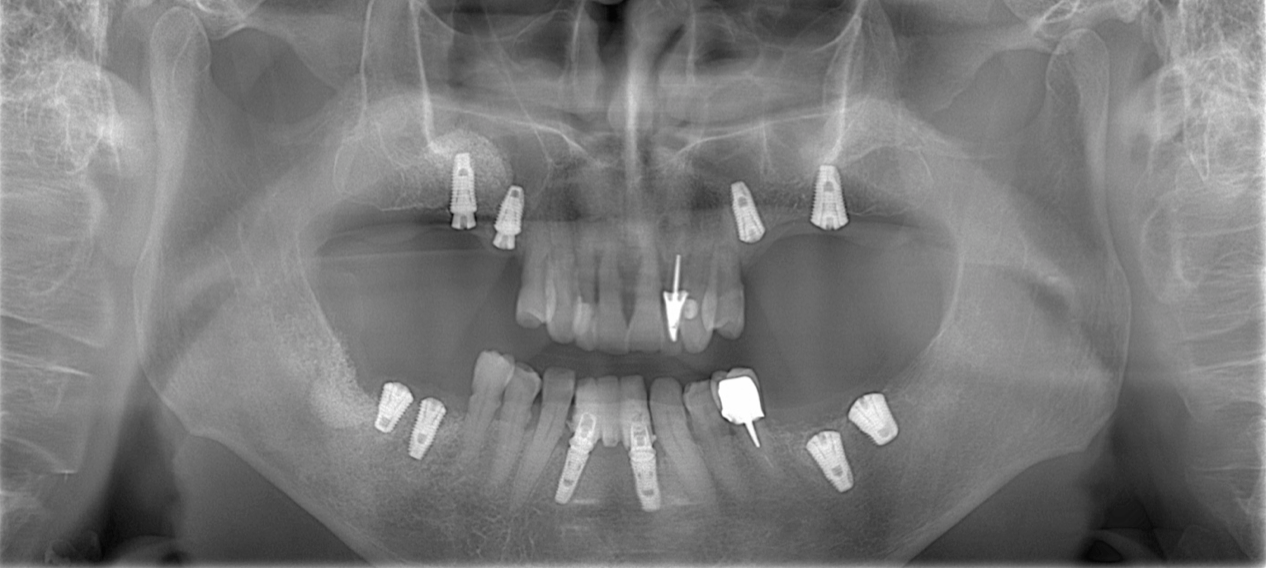

Cas numero 2 :

Situation Initiale

Etude du cas et proposition

Cas terminé

Les implants

L’implant dentaire permet de recréer une nouvelle racine artificielle, là où manque(nt) une ou plusieurs racines. Il peut être utiliser comme support pour remplacer une ou plusieurs dents manquantes (couronne ou bridge), ou comme attachement sous un appareil amovible (pour le stabiliser).

L’implant va se fixer dans l’os, et nécessite quelques explorations pour déterminer la possibilité de la réalisation. Il existe des contre-indications à la pose d’ implant, et la décision ne se fera qu’après réflection et prise en compte de tous ces éléments.

Après un laps de temps compris entre 3 et 6 mois (variable selon le cas et la qualité osseuse), l’implant sera instrumenté, et on pourra enfin lui donner une fonction au sein de la cavité buccale.

Il arrive que nous soyons obligés d’avoir recours à une intervention supplémentaire, pour permettre la pose des implants. Cela peut prendre la forme d’une ROG (régénération osseuse guidée) ou d’un relevé de sinus. Ces deux interventions se pratiquent couramment, et seul leur nom doit faire peur.

Chirurgie Guidée

L’implantologie moderne évolue vers un positionnement des implants dicté par la prothèse. Il permet et garantit un meilleur résultat esthétique, une meilleure distribution des forces et une hygiène facilitée. La combinaison de l’imagerie 3D et de logiciels de planification autorise des études préliminaires d’une grande finesse. On pourra ainsi visualiser la faisabilité prothétique d’un plan de traitement implantaire.

Au cabinet, pour les cas complexes, après réalisation d’une imagerie 3D (scanner ou cone beam), le cas sera étudié (avec un logiciel de planification), et une solution sera proposée. Dès validation, un guide chirurgical sera confectionné, dans l’absolu respect de la planification. Il permettra de positionner et placer chaque implant dans la position et l’axe pré-défini.

Plusieurs types de guides sont possibles. S’il reste des dents sur l’arcade, nous réaliserons un guide dento-porté (stable et précis). S’il ne reste aucune dent, nous devrons réaliser un guide ostéo-porté.